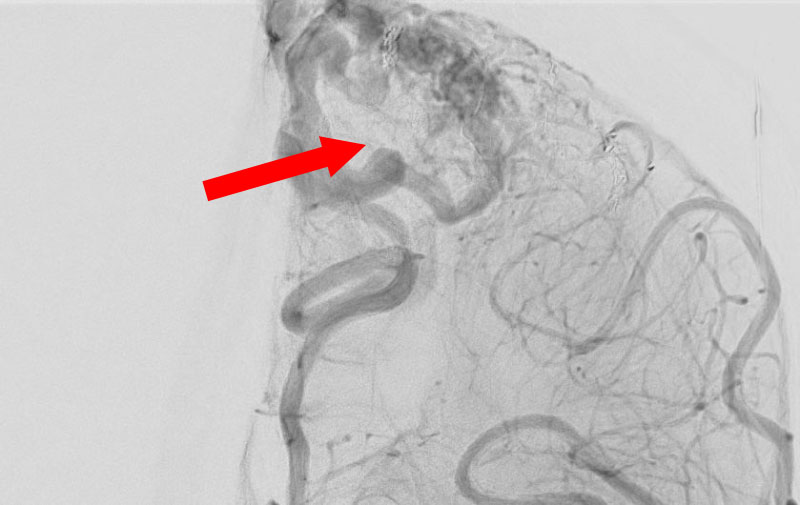

No.1590 手術前

'25年10月

左総頚動脈狭窄症

30代

院内外来